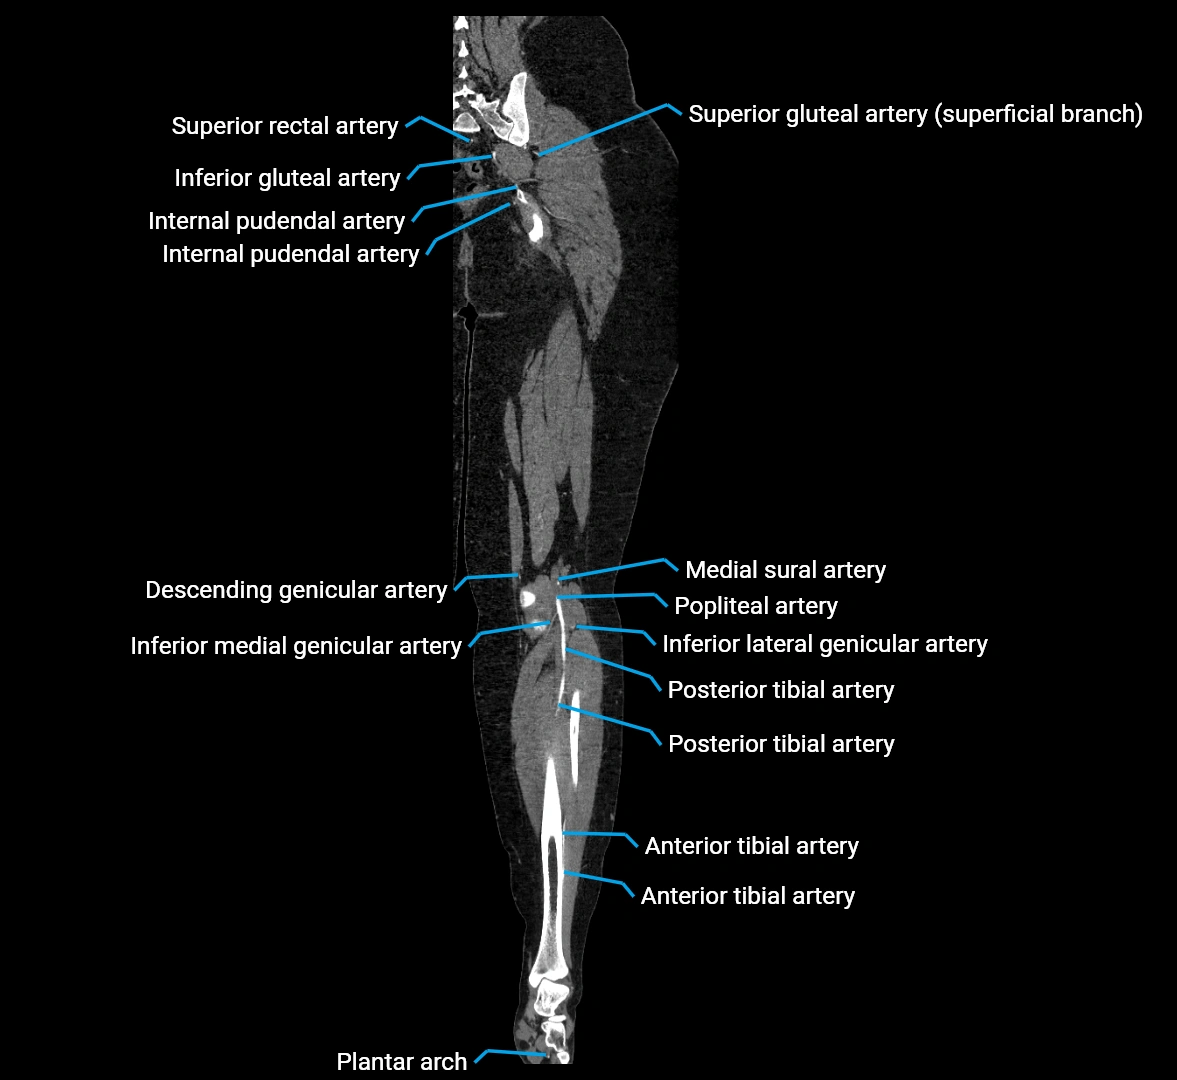

CT Appearance

Non-contrast CT:

• Appears as a tubular soft tissue structure anterior to vertebral bodies

• Calcified atherosclerotic plaques appear as hyperdense foci along the wall

• Useful for screening abdominal aortic aneurysm (AAA) size and mural calcification

Contrast-enhanced CT (CTA):

• Gold standard for abdominal aortic imaging

• Provides excellent detail of lumen, wall, aneurysm, thrombus, and branch vessels

• Multiplanar and 3D reconstructions help in aneurysm measurement, stent graft planning, and dissection evaluation

• Detects acute rupture, traumatic injury, or occlusion with high sensitivity